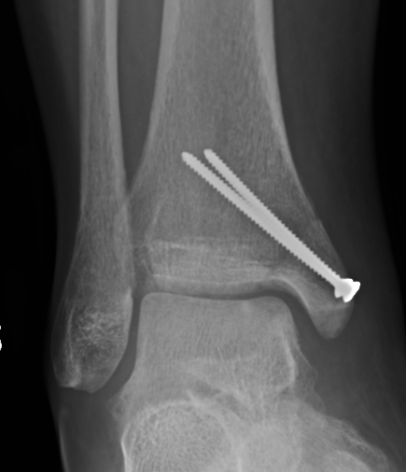

Medial Malleolar osteotomy

Predrill for screws

Arthrotomy / image guidance

Posterior homan to protect tibialis posterior

Initial osteotomy with saw / complete with osteotome